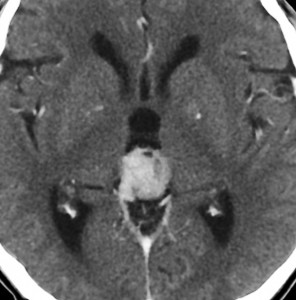

第3脳室開窓後のCTです。左のCTでは小さな石灰化がみられます。右の造影CTでは小さなのう胞部分をのぞいて均一な増強効果がみられます。

MRIガドリニウム増強像です。腫瘍境界がわりにはっきりしていて,中脳や視床に浸潤像がありませんから,松果体芽腫ではないことが解ります。でも,この画像だけからは,松果体細胞腫やジャーミノーマとの区別はつきません。